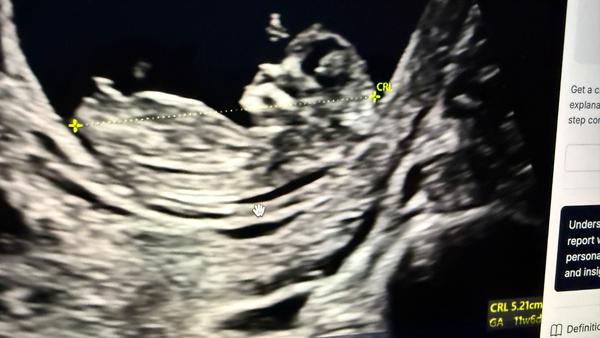

Může někdo určit pohlaví podle ultrazvuku ve 13+3 týdnu?

@hollynka těžko říct, jestli to co je vidět je pohlavní hrbolek, tak je to holčička. Já si podle něj sama určila tenkrát dceru 😁teď jsem to věděla z NIPT. Jsou lékaři, co se trefí už ve 13 tt, co to umí. A pak jsou i lékaři, kteří i kolem 20 tt vahaji.

Mě přijde, ze holka.

@hollynka myslim si, ze holka 🤗